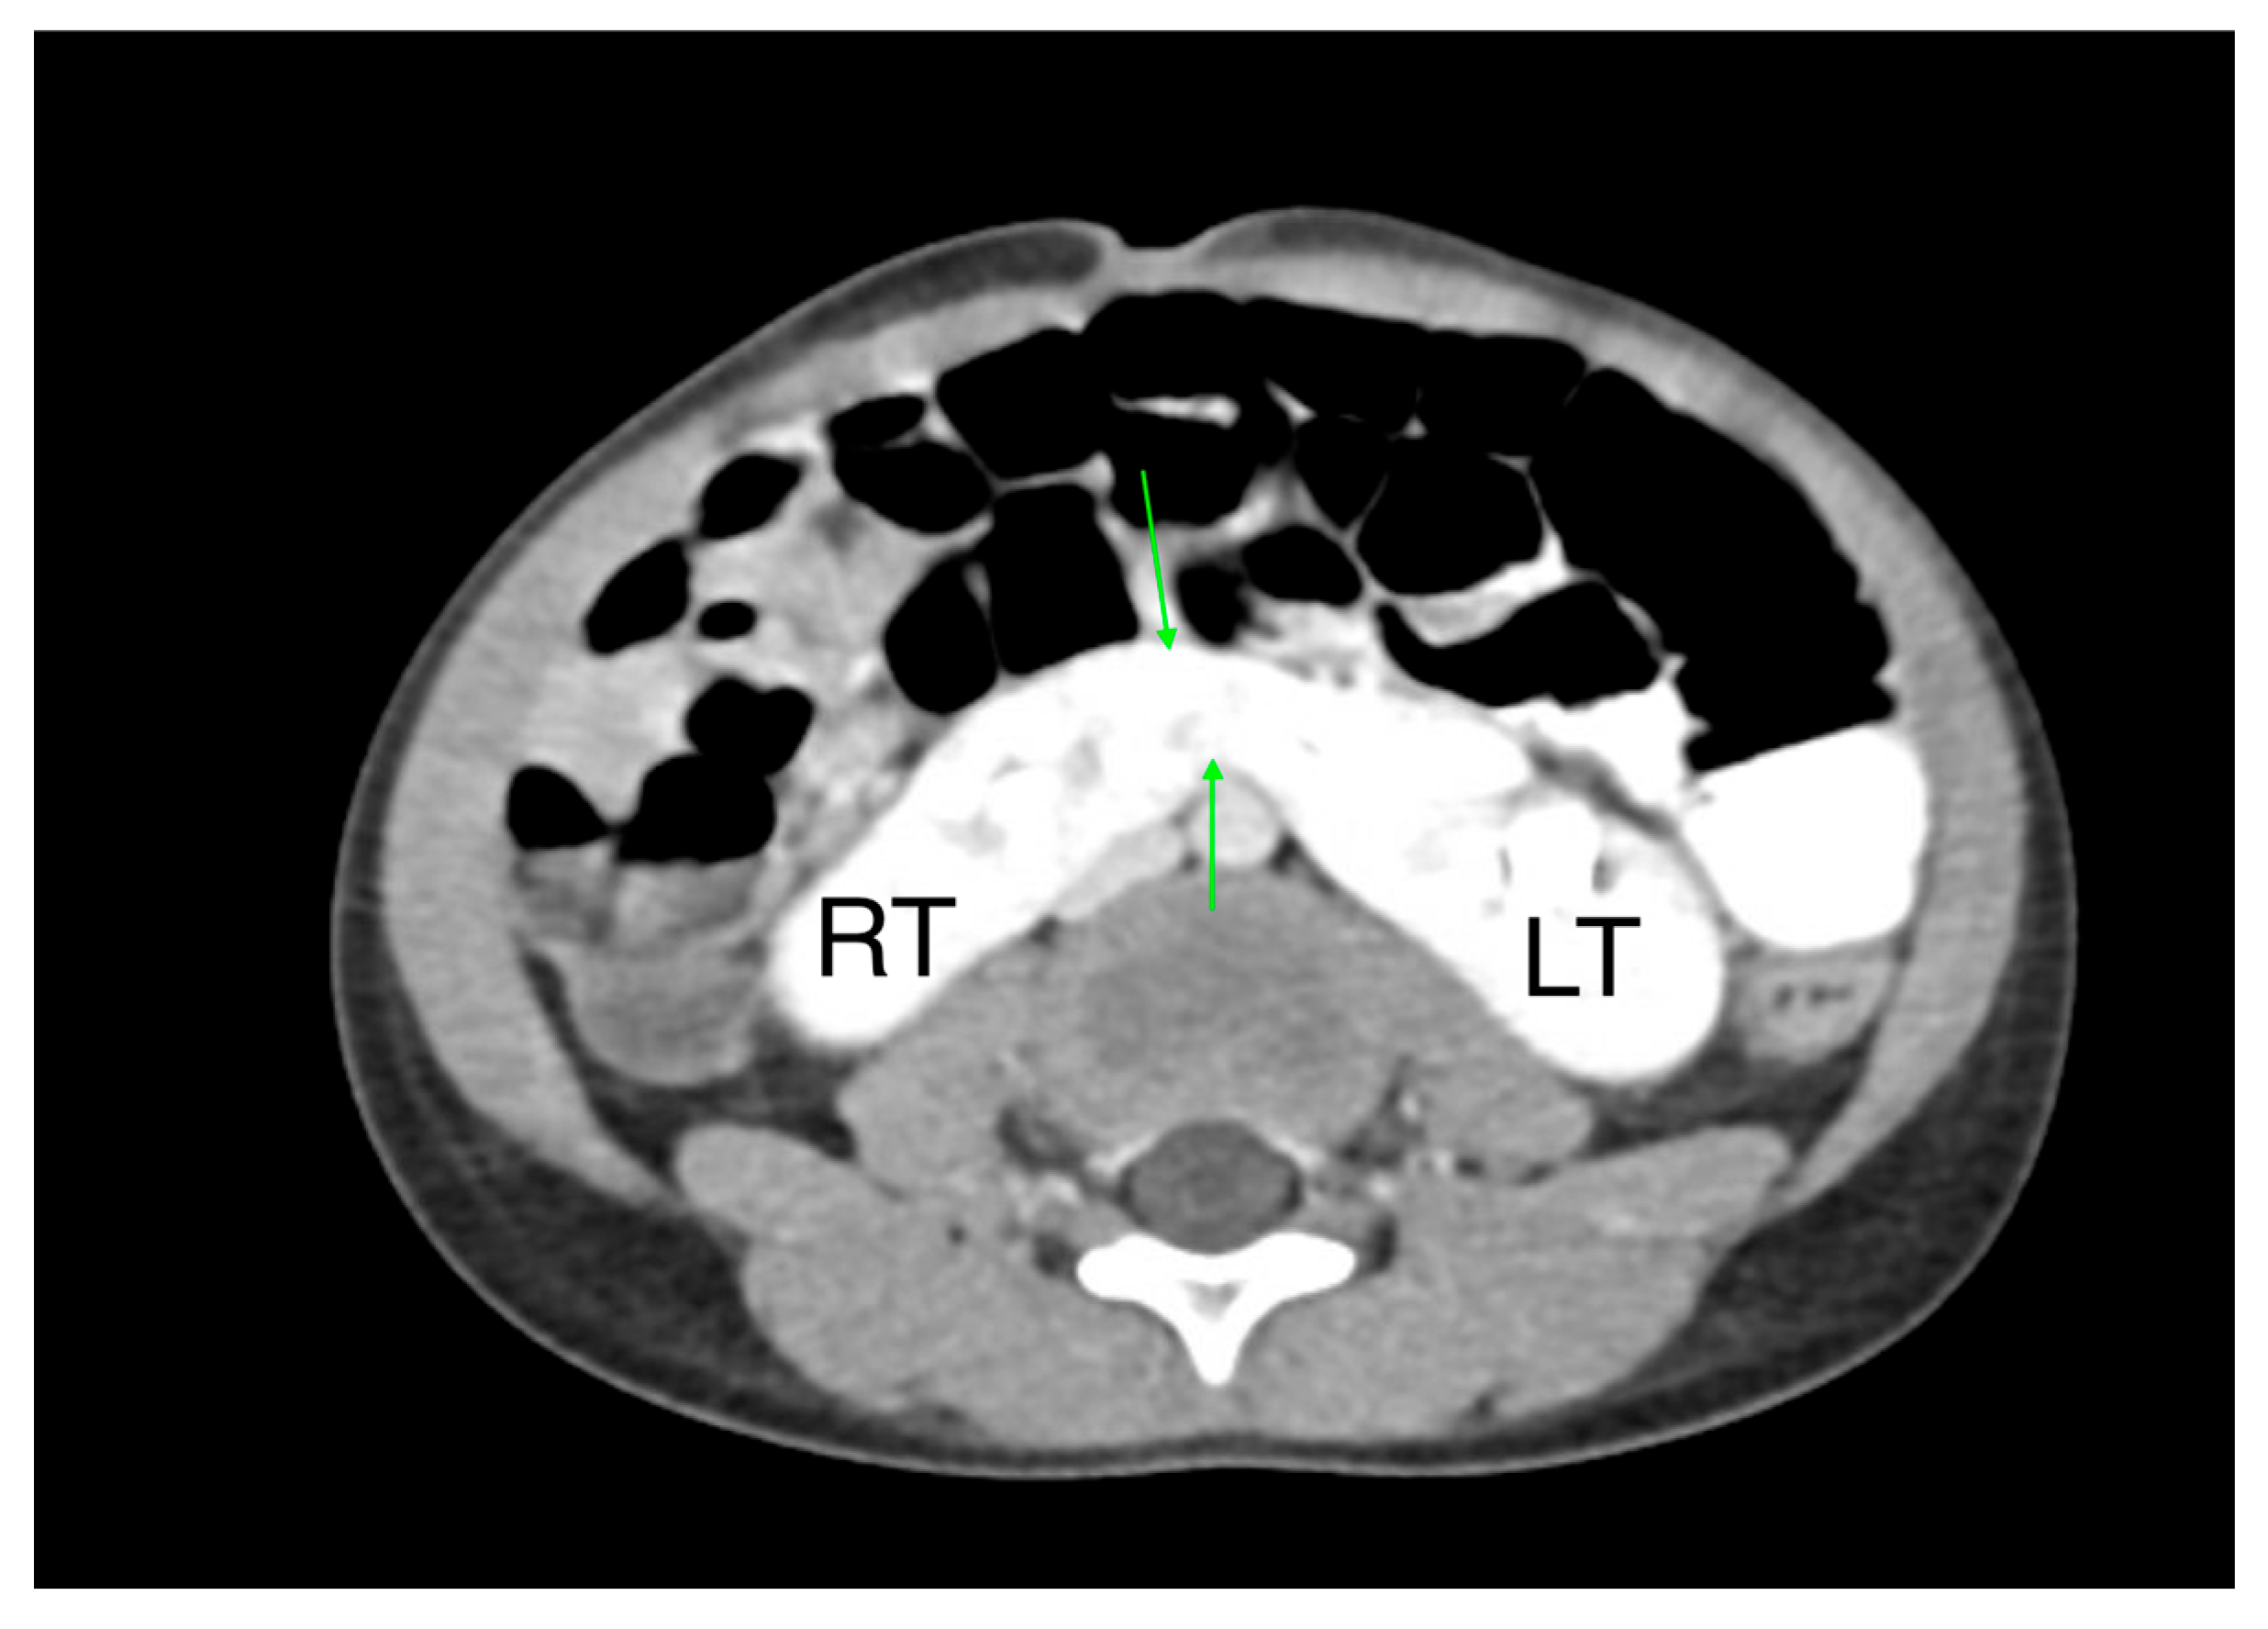

- A horseshoe kidney is the most common renal fusion anomaly, occurring in about 1 in 400 live births. In this condition, both kidneys are fused at their lower poles, forming a “horseshoe” shape (Figure 14)

- Renal ectopia occurs in approximately 1 in 900 births and is typically unilateral. In about 40% of cases, the ectopic kidney is located in the pelvis. Crossed ectopia occurs when one kidney crosses the midline and fuses with the other, often resulting in a “crossed-fused” appearance.